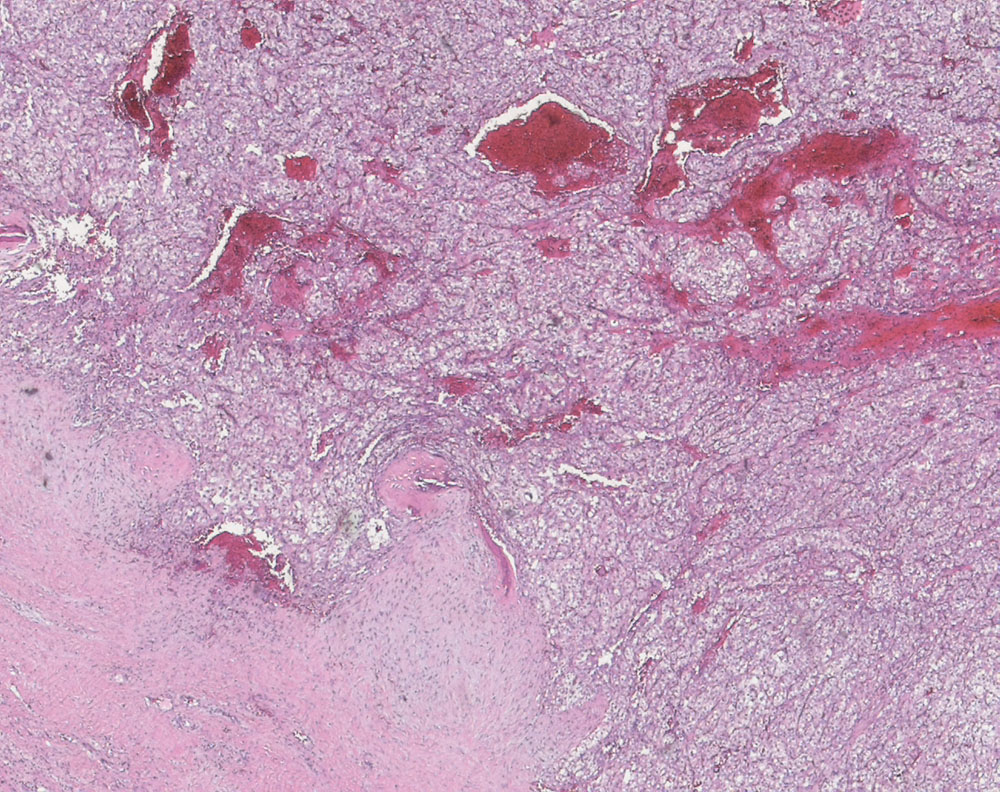

Follikuläres Schilddrüsenkarzinom klarzellige Variante

Solid-trabekulär wachsendes hellzelliges Adenokarzinom. Die Morphologie der Metastase erinnert stark an ein hellzelliges Nierenzellkarzinom.

Immunhistochemie: Thyreoglobulin diffus und kräftig positiv, Vimentin positiv, CD10 fokal positiv, Renal Cell Carcinoma negativ

Metastasierendes follikuläres Schilddrüsenkarzinom. Thoraxwandmetastase.

Carcinomas composed of a variable proportion of clear cells, oxyphil cells, and cells with combined oxyphil and clear cell features are included in the category of oxyphil cell variant of follicular carcinoma. The biologic behavior of these tumors is consistent with that of follicular carcinomas. The clear cell change could be the result of chronic TSH overstimulation. This may explain the variable histological patterns, nuclear features, and biologic behavior associated with these tumors. These tumors bear a striking histologic resemblance to metastatic renal cell carcinoma and clear cell neoplasms from other sites. Immunocytochemical stain for thyroglobulin proved to be a specific and sensitive method for identification of these tumors.